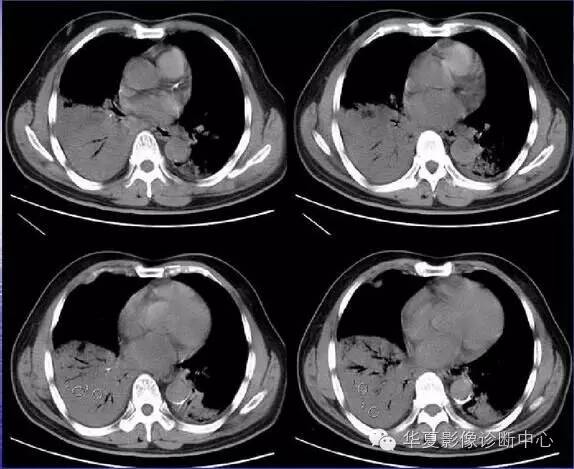

小叶性(支气管性)

肺炎病原体经支气管人侵,引起细支气管、终末细支气管及肺泡的炎症,常继发于其他疾病,如支气管炎、支气管扩张、上呼吸道病毒感染以及长期卧床的危重患者。其病原体有肺炎链球菌、葡萄球菌、病毒、肺炎支原体以及军团菌等。支气管腔内有分泌物,故常可闻及湿性啰音,无实变的体征。X线显示为沿肺纹理分布的不规则斑片状阴影,边缘密度浅而模糊,无实变征象,肺下叶常受累。